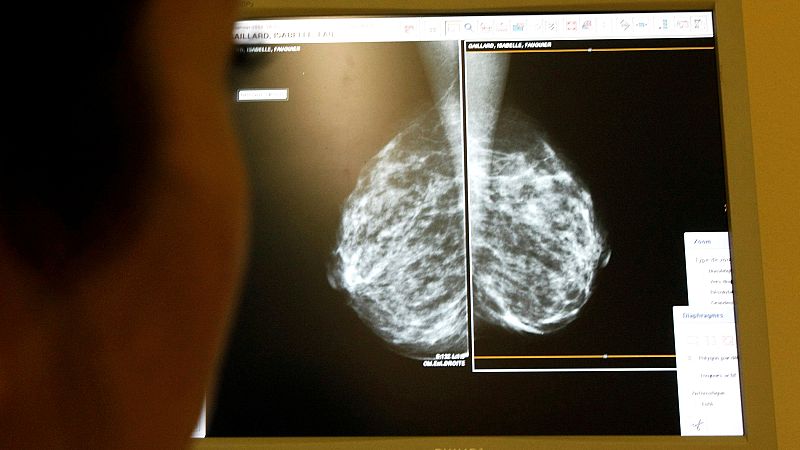

- La vacunación es especialmente eficaz entre los 15 y los 26 años

- En mujeres de entre 25 y 45 años, no protege tan bien

- Los datos corresponden a 73.000 mujeres, durante los últimos ocho años